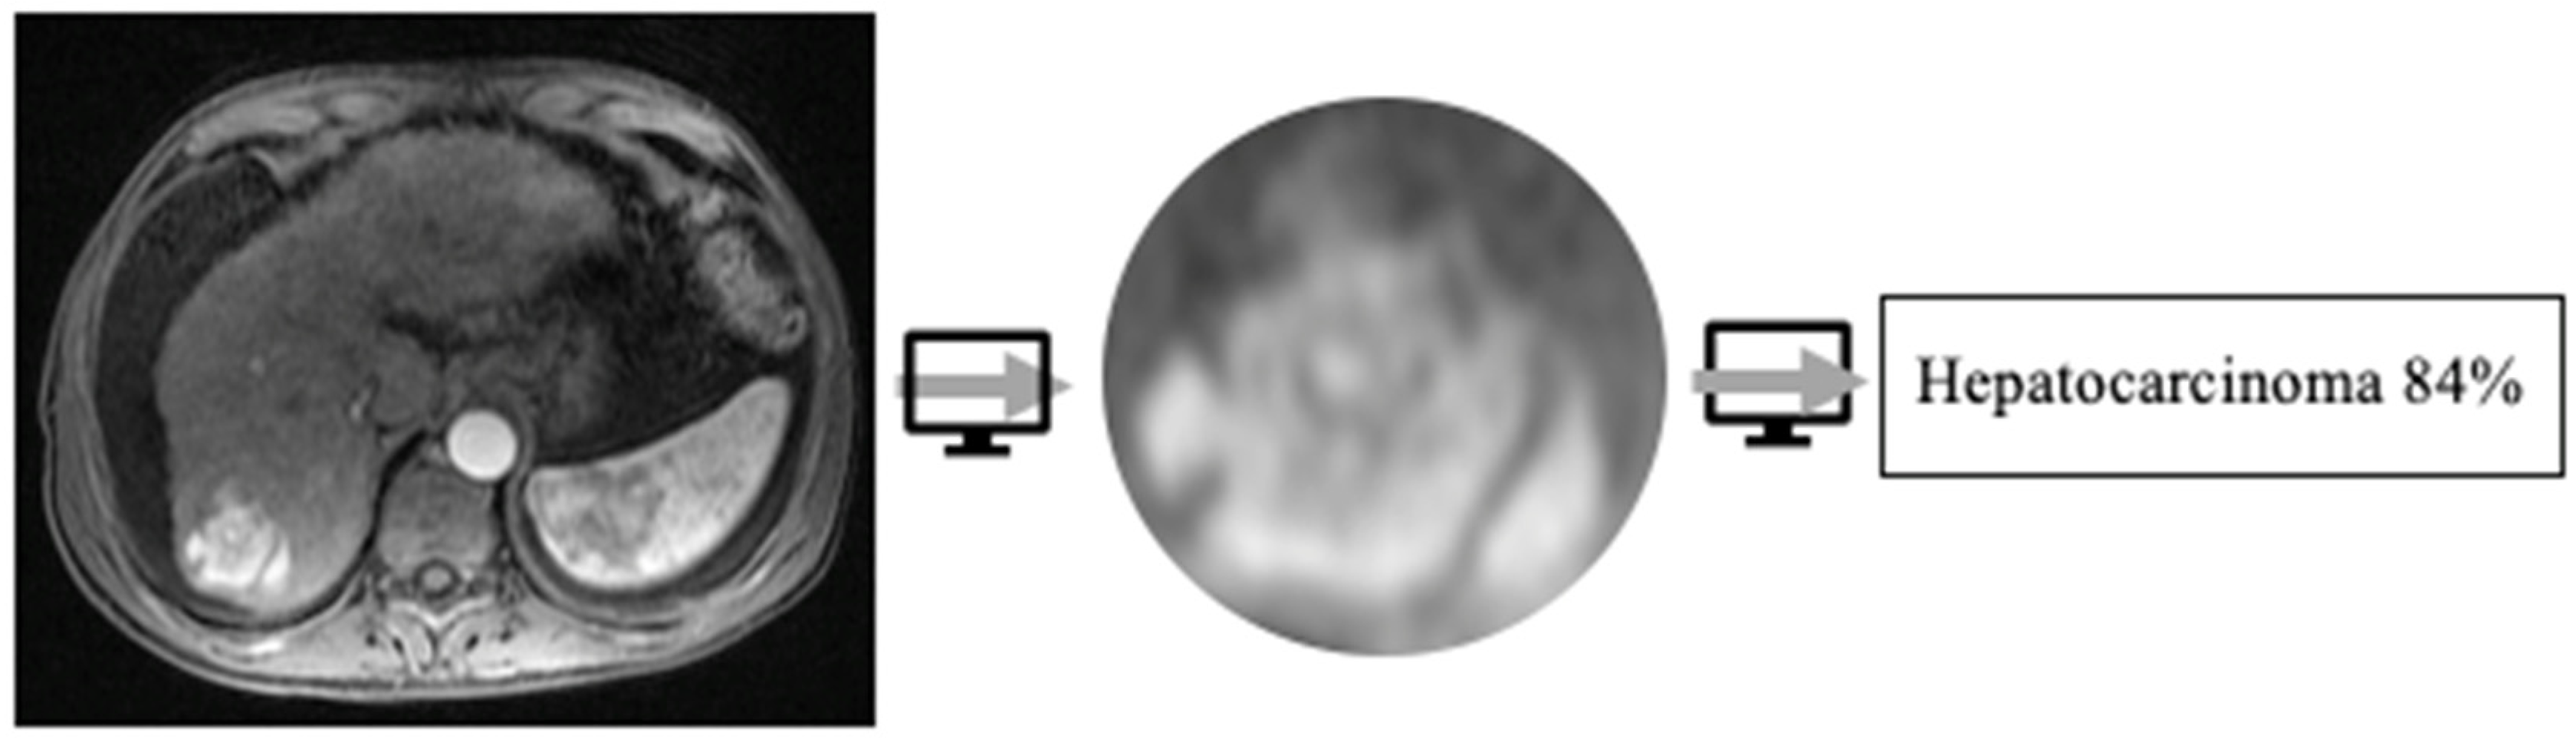

4.2. Segmentation

| Jimenez-Pastor et al. [69] | 2021 | Liver segmentation, fat, and iron quantification | MRI | DL (CNN) | 93% |